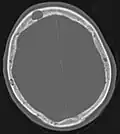

Rayons X

Pour le diagnostic initial, la radio X classique a une importance centrale. L'indication pour des projections sur deux plans est toujours donnée en cas de soupçon de tumeur osseuse[87]. Les métastases ostéolytiques sont caractérisées par une perte de densité osseuse. Ceci se reconnaît sur la radio par un noircissement plus élevé, en raison de la plus grande transparence aux rayons X. Inversement, les métastases ostéocondensantes présentent à cause de la plus grande densité osseuse un noircissement inférieur. Les métastases ostéolytiques sur la colonne vertébrale sont nettement plus difficiles à reconnaître : seulement quand environ 50 % de la densité totale de l'os a disparu[87].

Scanner d'une métastase ostéocondensante dans l'os du crâne d'un patient souffrant d'un carcinome de la prostate. On reconnaît clairement l'extension de la métastase au-delà des limites initiales de l’os.